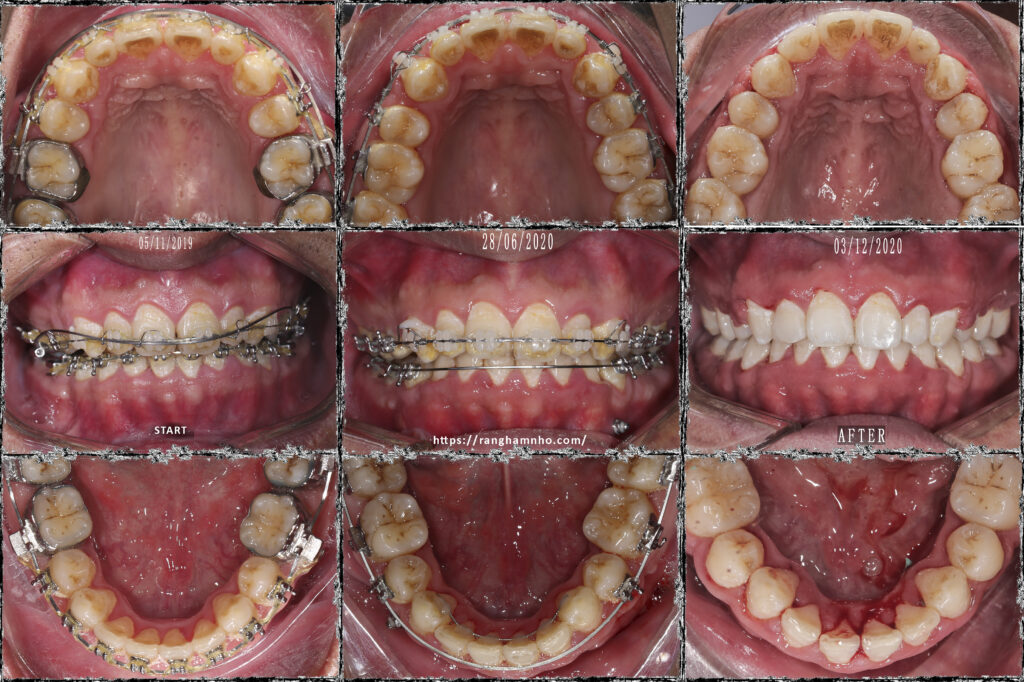

Điều trị những trường hợp bật chân răng do niềng hỏng là rất khó khăn và phức tạp. Trường hợp này là một bệnh nhân được niềng răng ở nước ngoài, sau đó hết thời gian lao động mà bệnh nhân chưa hoàn thành điều trị và được chuyển về việt nam để điều trị tiếp. Tuy nhiên, khi BN đến với phòng khám làm gặp tình trạng mất torque rất nặng ở hàm dưới đến mức trên CBCT không còn cả bản xương ngoài- trong. Nên nhóm răng cửa hàm dưới không thể can thiệp gì hơn.

Kế hoạch: chỉnh torque, đóng nốt khoảng và chỉnh khớp cắn 2 hàm, hoàn thiện và kết thúc trong 1 năm

Kết quả cười hở lợi cải thiện rõ rệt. Điều trị cười hở lợi bằng chỉnh nha khá hiệu quả trong trường hợp này